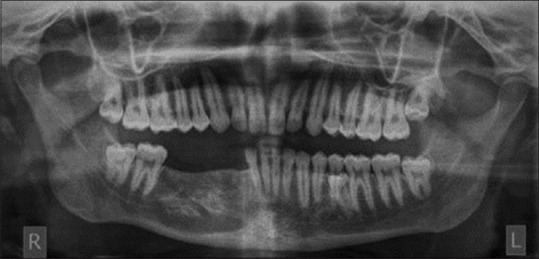

Mandibular ameloblastoma are rare, noncancerous tumors which originate from odontogenic epithelium. Ameloblastoma, commonly occurring in the mandible, disturbs its balance and symmetry. Surgical treatment of ameloblastoma though gets rid a patient of the tumour, but it may also result in compromised esthetics and function. The present case report focuses on the implant-supported rehabilitation of the mandibular region treated with surgical enucleation of the tumour.